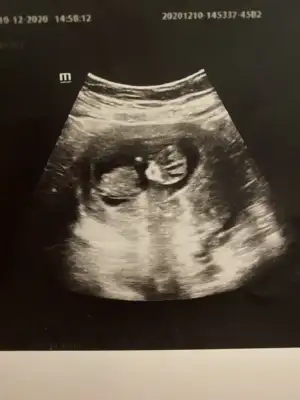

dr soylemeden siz gorun genital nub teorisi ( bebegin cinsiyeti)

Erkek ve kız için 11 + 12+ yada 13 hafta usg görüntüsü olmalı açıklamalar asagıda yazıyor 😊 rabbim herkesin gönlüne göre nasip etsin inşallah .. ecmain

[/B]Eki Görüntüle 473828 gordugunuz gibi ust taraftaki simgedende anlasildigi gibi eger cikinti paralel ise kiz

yok 30°lik bir aciyla yukari dogru bakiyorsa %99 oglunuz olacak demektir simdi bi kac ornek resimler daha koyacagim kiziminkide dahil

Eki Görüntüle 473831 simdi burada cikintilara bakin eger bel popo cizgisine paralel ise kiz

yok 30 derecelik bir aciyla yukari bakiyorsa erkek

Eki Görüntüle 473837 bu benim kizim cikinti gayet net ve ortada ve ben kizim diyooo